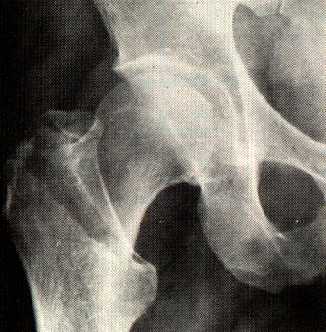

Paciente de 87 años que ingresa de urgencias con una fractura fenoral inter-trocantérica izquierda.

Gamma nail versus compression screw for trochanteric femoral fractures. 15 reoperations in a prospective, randomized study of 378 patients.